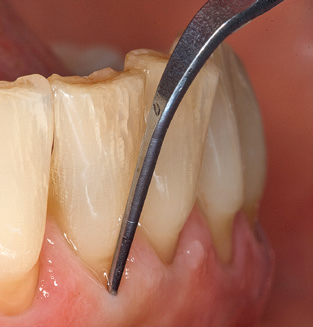

Die gute Ausleuchtung des Arbeitsfeldes stellt eine wesentliche Erleichterung dar. Bei dem von den Autoren genutzten System ist dies gelungen, indem ein 5­facher LED­Ring in das Handstück integriert wurde. Natürlich werden für dieses System unterschiedliche Arbeitsspitzen für die jeweiligen Indikationsbereiche angeboten. Eine gerade, universell einsetzbare Spitze ist das Basisinstrument zur maschinellen Instrumentierung natürlicher Zähne (Abb. 5a und b). Für schwer zugängliche Bereiche im Seitenzahnbereich werden gebogene Spitzen angeboten, die auch einen Zugang zu freiliegenden Furkationen ermöglichen (Abb. 6).

Abb. 4: Für das Sondieren an dentalen Implantaten sind biegsame, millimeterskalierte Sonden empfehlenswert (z.B. Colorvue Kit PCV11KIT6, Hu-Friedy). – Abb. 5a und b: Eine gerade Arbeitsspitze (1P, W&H Dentalwerk Bürmoos GmbH) ist universell für die Instrumentierung natürlicher Zähne geeignet. – Abb. 6: Für die Bearbeitung schwer zugänglicher Bereiche der Zahn- und Wurzeloberflächen (z.B. Furkationen) bieten sich gebogene Arbeitsspitzen (3Pr/3Pl, W&H Dentalwerk Bürmoos GmbH) an. – Abb. 7: Die spitz zulaufende sechseckige Implantatreinigungsspitze (1I, W&H Dentalwerk Bürmoos GmbH) ermöglicht eine atraumatische und effiziente Reinigung der Kronen- und Abutmentoberflächen. – Abb. 8: Für die manuelle Instrumentierung der Implantatoberflächen sind Titan- oder Carbonküretten geeignet.